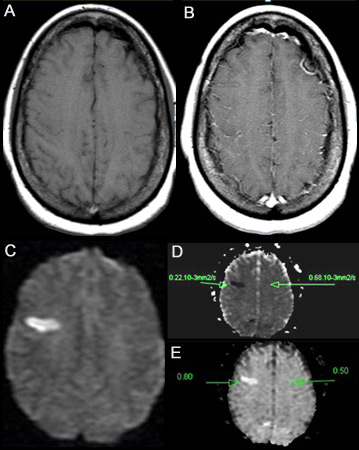

Acidente vascular cerebral (AVC) isquêmico

(A) Imagem por ressonância magnética nuclear (IRM) ponderada em T1 sem contraste. (B) IRM ponderada em T1 pós-contraste mostrando aumento mínimo em vasos leptomeníngeos na região frontal direita. (C) Imagem ponderada por difusão (DWI) mostrando uma área hiperintensa na região frontal direita. (D) Mapa de coeficiente de difusão aparente (CDA) mostra a lesão hipointensa, indicando difusão restrita que correlaciona com alta intensidade em IPD e difusão exponencial. (E) O valor do CDA é 0.22 x 10¯³ mm²/segundo, correspondente a um infarto hiperagudo

Do acervo pessoal do Dr. Eric E. Smith; usado com permissão